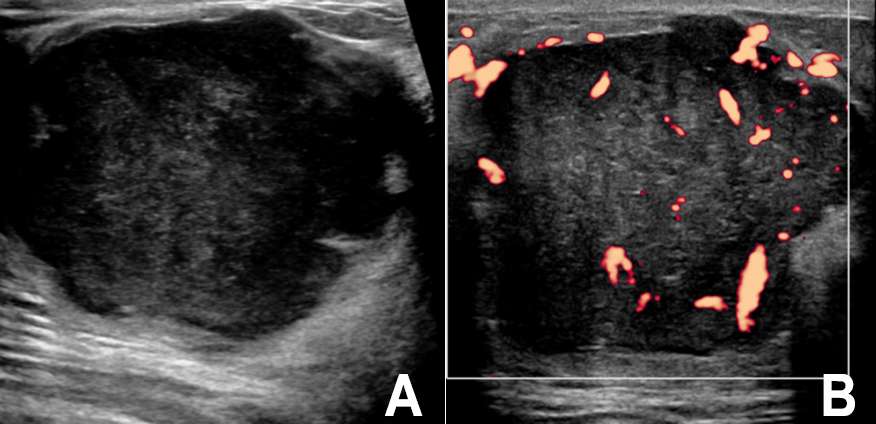

Ultrasound

As with mammography, the sonographic appearance of breast sarcoma is nonspecific. Breast sarcomas may be oval, hypoechoic or mixed echogenicity masses with microlobular or indistinct margins. They often demonstrate internal vascularity and posterior acoustic shadowing4 (Figure 2).